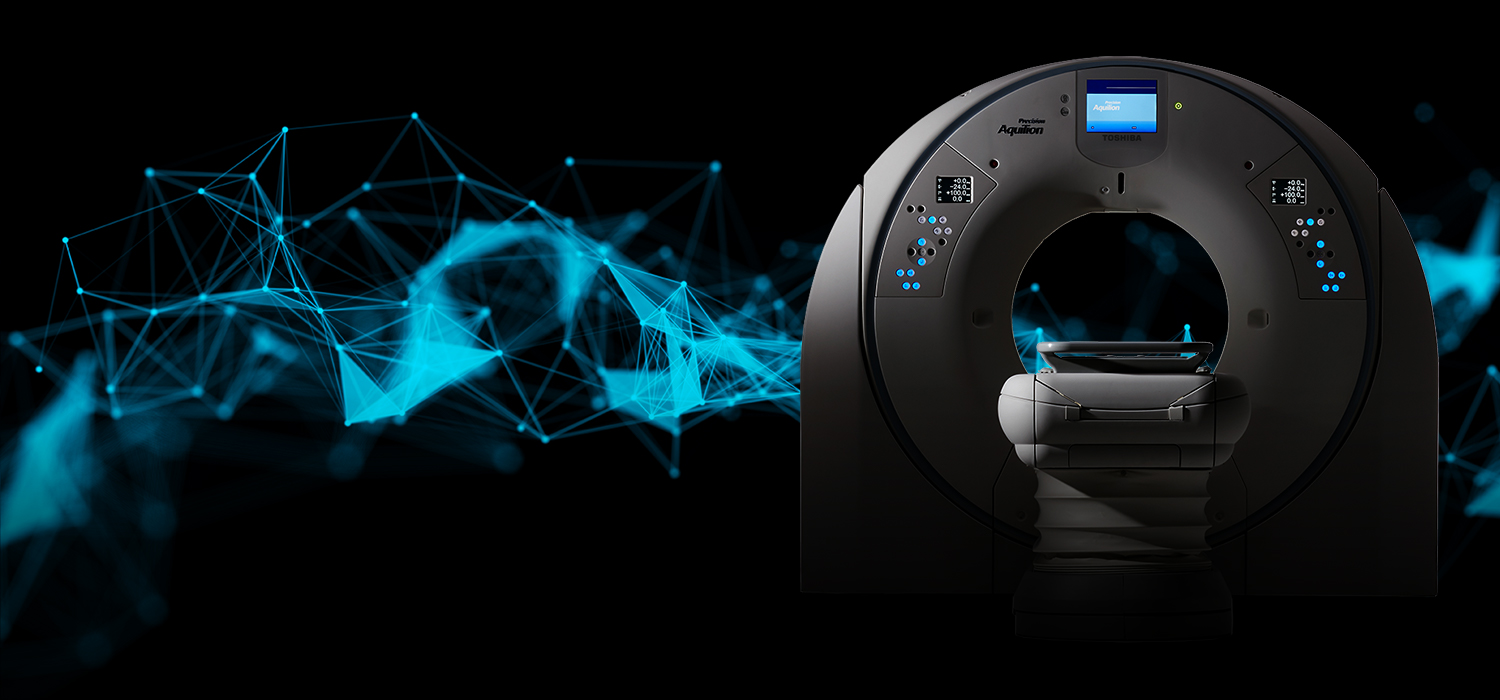

www.shutterstock.comCT Scanner Isolated On Background. 3d Rendering - Illustration 37363840 PNG

www.shutterstock.comCT Scanner Isolated On Background. 3d Rendering - Illustration 37363840 PNG

www.istockphoto.comCT Scanner Isolated On Background. Ideal For Large Publications Or

www.istockphoto.comCT Scanner Isolated On Background. Ideal For Large Publications Or

www.worldcitimedicalcenter.comCt Scanner Isolated On Blurred Ct Scan Room Background Stock Photo

www.worldcitimedicalcenter.comCt Scanner Isolated On Blurred Ct Scan Room Background Stock Photo